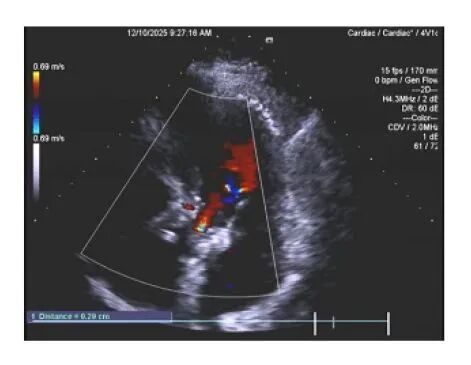

内容提要 近日,葫芦岛市第二人民医院心脏中心在常务副院长、心脏中心主任张占修的带领下,联合辽宁省人民医院副院长、著名心血管专家栾波教授,成功为一例病情复杂危重的高龄心脏疾病患者,实施了经导管主动脉瓣植入术(TAVR)。术后患者恢复良好,标志着我中心在高危心脏瓣膜病微创介入治疗领域取得又一重要突破,让本地患者在家门口即可享受与国家标准同质的顶尖技术服务。 老年男性患者,自述心脏病史长达二十年,病情极为复杂。患者曾因心肌梗死先后植入7枚支架。近期胸痛、胸闷、气短症状反复发作,检查发现主动脉瓣重度狭窄,生命健康受到严重威胁。 术前超声及诊断 面对患者复杂的心脏病史,张占修院长迅速组织多学科会诊,联合心脏血管外科李寒教授、血管介入科田明主任等专家深入评估,审慎研判传统开胸手术的高风险性,最终决策采用微创TAVR技术,以最小创伤化解危机。 经导管主动脉瓣植入术(TAVR)是心脏介入领域的一项革命性技术。它通过血管穿刺路径,将压缩的人工瓣膜输送至心脏病变部位并释放,从而替代原有病变瓣膜的功能。该技术具有创伤小、无需开胸、心脏不停跳、术后恢复快等优势,尤其适用于高龄、高危及不能耐受传统外科手术的患者。 手术当日,张占修院长团队携手辽宁省人民医院副院长栾波教授共同实施手术。术中以右侧股动脉为主要操作通路,在数字减影血管造影(DSA)的实时透视引导下,团队精准完成了导管导丝跨主动脉瓣操作,建立稳定手术轨道。依据术前精细的CT影像测量与术中造影结果,选择了尺寸最匹配的人工主动脉瓣膜,并输送至预定位置。辅以临时起搏器快速起搏以暂时阻断血流,精准完成人工瓣膜的扩张释放。术中影像显示,瓣膜支架展开完全,位置理想,植入即刻效果显著。术后患者血流动力学迅速趋于稳定,安返心脏重症监护室(CCU)。 术后复诊超声 术后患者生命体征平稳,在心脏中心医护团队的精心照护下恢复顺利。术后一月复查心脏超声显示,人工瓣膜位置固定良好,功能完善,未见瓣周漏,主动脉瓣前向血流明显改善。困扰患者多年的胸痛、胸闷、气短等症状完全消失,心功能及生活质量得到了质的提升。此次手术的成功,充分体现了TAVR技术对于复杂高危患者的救治价值。 葫芦岛市第二人民医院心脏中心始终秉承“以患者为中心”的服务理念,在心血管疾病治疗领域持续深耕,不断实现技术突破。近年来,中心在不断提升自身核心技术水平的同时,积极构建高水平医疗协作网络,与北京安贞医院、北京阜外医院、北京大学人民医院、辽宁省人民医院等国内多家知名三甲医院建立了长期、深入的技术合作关系。通过定期邀请国内顶尖专家来院手术、会诊、授课,以及选派骨干医师赴名院进修学习,实现了技术、理念与资源的同步更新。 这种“引进来、走出去”的开放模式,确保了中心始终紧跟国内外诊疗前沿进展,将最先进的技术和诊疗方案引入滨城,让以往需要远赴北上广的疑难、危重心脏疾病患者,在本地就能得到国家级标准的诊断与救治,为滨城百姓的心脏健康筑起了一道坚实、可靠的技术屏障。 特聘著名专家 栾波 医学博士 主任医师 博士研究生导师 ·辽宁省人民医院副院长 ·中华医学会心血管病学分会第十二届委员会委员 ·辽宁省心血管病预防与控制专业第三届委员会主任委员 ·辽宁省医学会心血管病分会第十届委员会副主任委员 专业特色:擅长危重冠心病及结构性心脏病介入治疗。率先完成东北首例冠状动脉“一站式”杂交手术、左心室辅助复杂PCI术、经皮主动脉瓣置换术,二尖瓣钳夹术等。特别针对复杂高危冠脉介入治疗,提出多种优化及创新方案,显著提高了手术成功率及安全性。主持国家级、辽宁省、市级课题9项,荣获辽宁科技进步奖3次,辽宁医学科技进步奖1次,辽宁医疗成果奖1次, 中国人民解放军医疗成果奖4次等,参编中国专家共识6篇,发表SCI等论文近50篇,著作8部。 院内著名专家 张占修 主任医师 教授 ·葫芦岛市第二人民医院常务副院长、心脏中心主任 ·中国健康管理协会心肺健康专业委员会常务委员 ·中国老年保健协会心血管专业委员会常务委员 ·辽宁省基层卫生协会胸痛中心建设专业委员会副主任委员 ·葫芦岛脑心同治专业委员会主任委员 ·葫芦岛市心电生理与起搏专业委员会主任委员 ·葫芦岛市心血管专业委员会副主任委员 学术荣誉:主编参编论著4部,主持参加国家省部级课题多项,发表论文30余篇。近年来相继组建了葫芦岛市心电生理与起搏学专业委员会、葫芦岛市脑心同治专业委员会;成立葫芦岛市第二人民医院专家工作站、葫芦岛市心脏病研究所、葫芦岛市首家心脏外科以及辽西地区首家心脏专科门急诊。 专业特色:在冠心病介入诊断和治疗、周围血管病介入治疗、永久起搏器安置术及顽固性心衰、高血压病、心律失常药物及射频消融治疗等方面取得了突出成绩。尤其在急诊介入救治急危急性心梗、复杂冠脉病变、左主干病变、慢性完全闭塞病变及支架内再狭窄的介入治疗方面有丰富经验和娴熟技术,多项新业务及技术填补本地区空白。 李寒 医学博士 主任医师 教授 ·葫芦岛市第二人民医院心脏中心副主任、心脏血管外科著名专家 ·原解放军总医院(301)第六医学中心心外科主任、北京中医药大学东直门医院心外科主任 ·北京医学会心血管外科分会委员 ·全军胸心血管外科学会青年委员 ·国家药品食品监督管理局医疗器械评审专家 ·北京转化医学会心外科分会常委 ·中国民族卫生医药学会心脏分会委员 专业特色:第三军医大学医学博士,从事心脏大血管外科30余年,擅长冠心病、瓣膜性心脏病、先天性心脏病、心脏肿瘤以及大血管病等心脏外科高难手术,包括:冠脉搭桥、瓣膜修复、置换,先心病矫治,主动脉夹层、动脉瘤外科手术,心脏肿瘤,外科手术中射频消融治疗心房颤动等,均在国内属于先进水平。 学术荣誉:长期致力于复杂心脏大血管外科治疗工作,参与偏远地区先心病患儿救治近4千例,并在国内开展了多项领先及高难技术,如冠状动脉旁路移植术中干细胞移植,干细胞移植治疗右室型心肌病、先心病合并重度肺动脉高压的诊断性治疗等。发表论文二十余篇,获得军队医疗成果奖两项。 田明 主治医师 ·葫芦岛市第二人民医院血管介入科副主任 ·中国医药教育协会中西医结合心血管专业委员会委员 ·葫芦岛市慢性创面修复外科分会委员 ·葫芦岛市心血管病分会委员 ·葫芦岛市心电生理与起搏专业委员会委员 ·辽宁省中西医结合学会介入心脏病学专业委员会委员 专业特色:冠心病复杂病变介入治疗、肥厚型梗阻性心肌病化学消融、下肢动脉硬化闭塞症、下肢静脉血栓、颈动脉狭窄、锁骨下动脉盗血综合征、肾动脉狭窄等外周血管疾病介入治疗、高血压、心衰、心肌炎等心血管疾病诊疗。